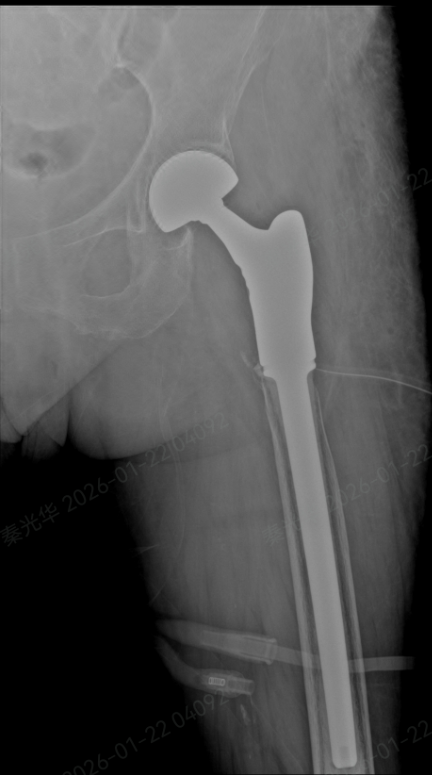

在神经电生理监测全程保障下,手术期间未出现任何并发症,假体位置良好、固定牢固,手术圆满成功。

术后X线影像检查

术后复查显示,张先生的人工髋关节位置正常,假体固定稳定,骨缺损修复效果符合预期,未出现感染、出血等并发症。后续将在康复团队指导下进行进一步功能训练。